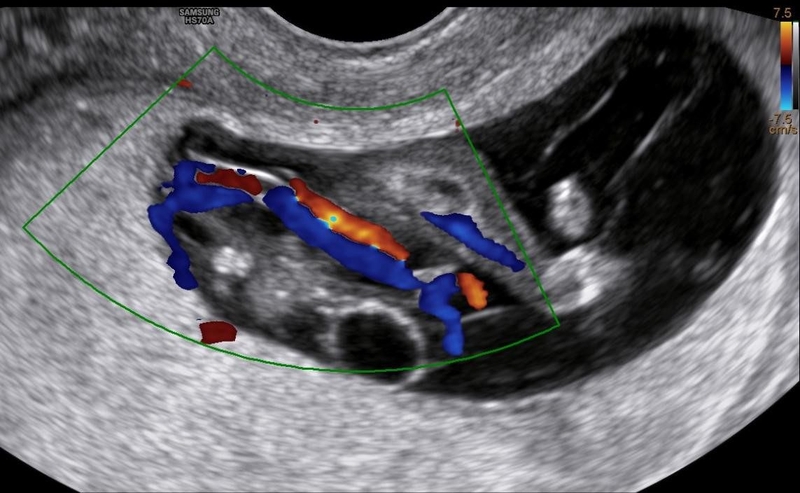

Có một số trường hợp điển hình của hội chứng dải sợi ối có thể được chẩn đoán bằng siêu âm trước khi sinh. Tuy nhiên, đa số các trường hợp chỉ được phát hiện khi trẻ mới sinh, thường là do các vấn đề về cấu trúc hoặc thiếu sót ở các phần của cơ thể.